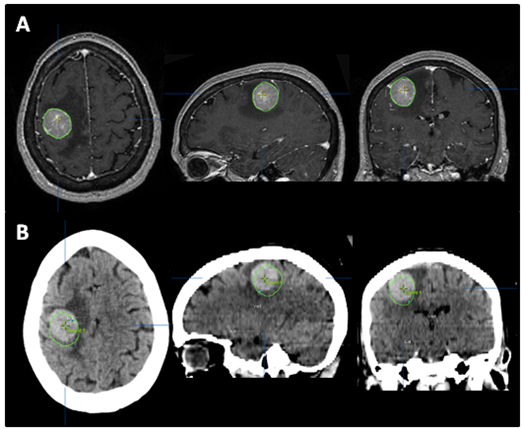

SRS is image-based treatment. All salient anatomic features of the SRS patient, both normal and abnormal, are commonly defined with CT and/or MRI. Both high three dimensional spatial accuracy and tissue-contrast definition are critical to the optimal definition of target(s) and critical structures for SRS. Imaging, whether CT or MRI, is crucial for localizing target boundaries as well as generating target coordinates for accurate treatment beam localization. Precise SRS treatment planning and delivery requires as a prerequisite that the target position is unchanged between image acquisition and treatment planning and delivery. In general, an intracranial target is not considered a moving target. Therefore, with rigid image registration and fusion, the MRI defined target and normal structures should accurately represent their relative physical position in space. Re-imaging of the brain is often done to evaluate for possible tumor progression, however, target migration between the time of imaging and treatment planning and delivery is typically not a concern. The present case illustrates a potential pitfall in the commonly made assumption that the location of the intra-cranial target is fixed in relation to the cranium and surrounding structures. In this study, the tumor position shifted within 12days, as shown in Figures 2 & 4. This resulted in a significant GTV mismatch of 3.312cc (28.3%) and a shift of the isocenter by 3.4 mm posteriorly, 0.3mm laterally and 2.5mm inferiorly (Figure 4). As demonstrated in Figure 5, if the pre-steroid MRI had been used for target delineation and planning, a significant portion of the GTV would not have been covered by the prescription dose (90% isodose line). The DVH confirmed that only 83% of GTV would have received the prescribed dose (Figure 6). Conversely, this could also have led to a significant overdose to the normal brain, in this case, the post central gyrus (Figure 2B) (Figure 2C). Quantitatively, 0.47cm3 more normal brain would have received the prescription dose of 16Gy, an increase of 17% compared to the treatment plan that the patient had actually received (3.24cm3 vs. 2.77cm3, respectively). Evidently, dexamethasone significantly decreased the peritumoral vasogenic edema, allowing the tumor to shift anteriorly and decompressing the post-central gyrus. If undetected, this would have represented the worst scenario for SRS, manifesting both inadequate tumor coverage, and extremely high normal tissue dose.

Figure 4 Tumor contour. The red line (narrow arrow) depicts the target contoured on the post-steroid MRI (A), which perfectly superimposed the tumor seen on the CT (B). The green line (broad arrow) represents the tumor contour based on the pre-steroid MRI. (C) depicts the superimposition of the two contours, and illustrates the magnitude of tumor displacement.